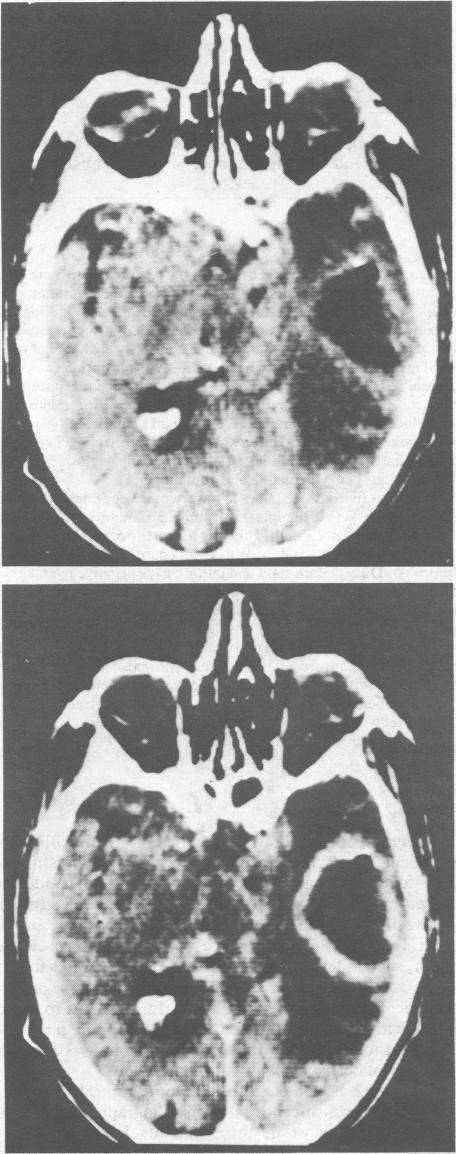

Brain abscess presenting as an intracranial gas shadow.

Br Med J (Clin Res Ed). 1987 Feb 7;294(6568):365-6. doi: 10.1136/bmj.294.6568.365.